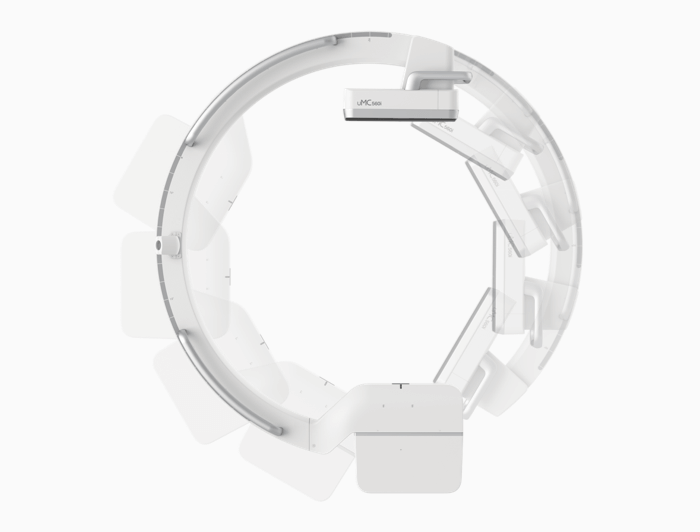

uMC 560i 使用高性能单晶硅平板探测器,成就术中高清动态影像;机架大开口与多种人性化功能,为骨科、消化内科、泌尿外科等科室医生提供灵活、开阔的手术空间,让术中操作得心应手。

为术者提供更大操作空间

85CM大开口设计

85cm大开口

同步触摸式双控屏

彩色标记运动轴

平衡设计